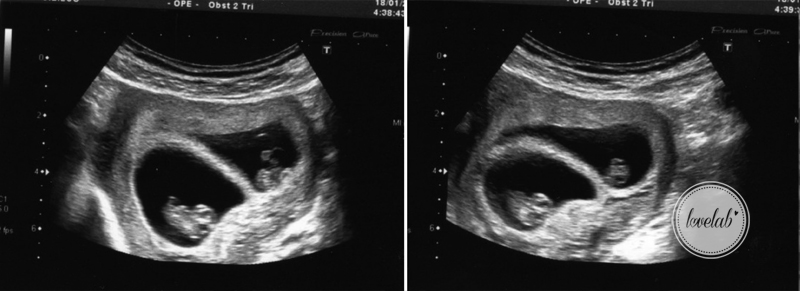

Estou nas 25 semanas + 3 dias e os bebés já estão virados para baixo. Calminha que ainda é cedo. Não tenham pressa. Isto cá fora é giro mas por enquanto a mala da maternidade ainda não está pronta!

Todos os parâmetros estão normais (que contente que ficamos). A menina continua a ser mais elegante. O peso do baby boy é de 777gr e da girl 721gr.

A imagem acima, diz respeito à primeira eco que fiz e onde se vê os dois sacos amnióticos, independentes um do outro. Foi esta eco que me fez insónias, no dia em que descobrimos que iam ser 2 em vez de 1! Nessa altura ainda eram uns seres milimétricos e agora já cresceram tanto. Estou assustada com as proporções que a minha a barriga ainda vai atingir (usar e abusar do creme na barriguita é essencial).